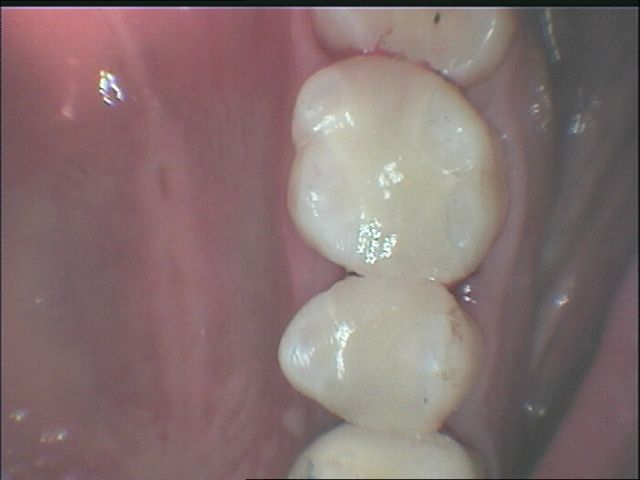

我們的新竹3D齒雕技術,是運用目前先進的牙科CAD-CAM設計,以專業的贋復技術整合電腦數位科技應用,精準地為每一位患者客製設計全瓷冠修復體,新竹3D齒雕能夠改善傳統傳統樹酯填補蛀牙的困擾,透過CAD-CAM數位整合運用,可精確計算患者的全瓷冠贋復需求,再利用專屬瓷塊車磨加工,讓牙齒看起來更為自然美觀,材質也接近人體的自然齒。

我們所提供的新竹3D齒雕結構緊密,咬合能力、硬度與耐用度都更勝傳統樹脂,只要是在正常的情形使用下,您比較不需擔心牙齒破裂、脫落等問題產生。

新竹晴美牙醫所打造的每一顆3D齒雕,都是一體成形的設計,我們採用由歐洲進口的瓷材,我們所使用的全瓷冠材質不含金屬成分、不易受熱脹冷縮的影響、與生物相容性高,由3D齒雕所填補的牙齒,接縫處看起來更為自然、也不易被察覺,新竹3D齒雕能夠讓牙齒看起來更美觀、並維持一定的穩定性,是您贋復時的理想選擇。